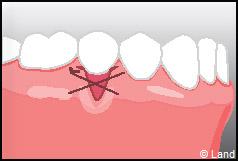

LES TECHNIQUES SANS APPORT DE GENCIVE :

Elles font appel à des lambeaux de gencive restante à proximité des récessions, qui sont déplacés et repositionnés sur la récession.

Dans ce cas le lambeau est déplacé latéralement pour combler la récession.